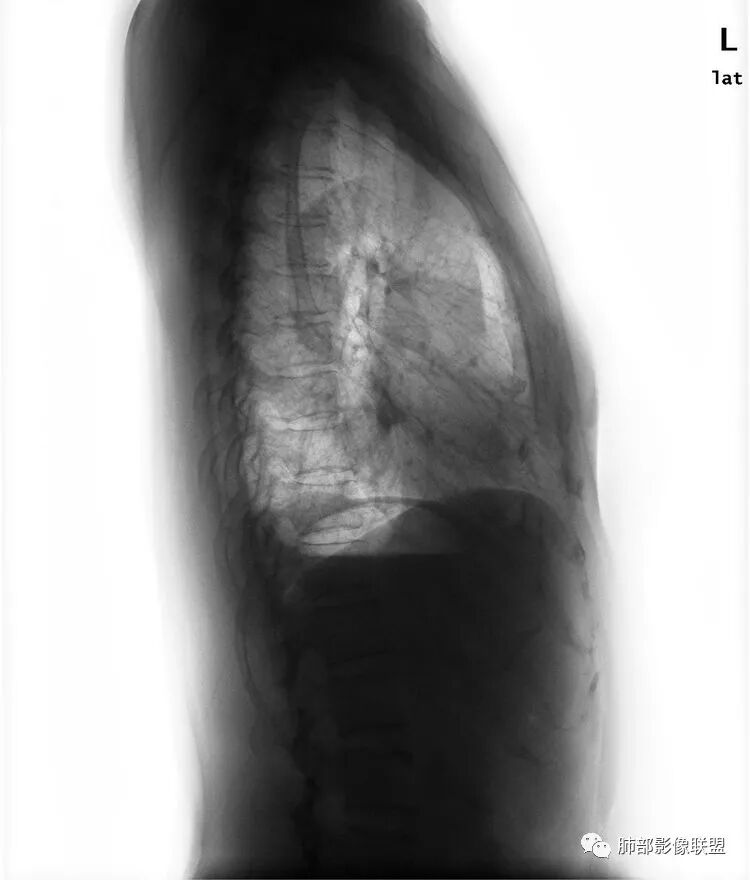

Shelia:侧位心后间隙变小,下肺野与心影重叠区怀疑有斑片影

正位实在看不出什么问题

Coke with ice:唉……我都没找出来病变在哪……平片的老师们指点指点南边:

Shelia:

南大标记的,我怀疑了,但是正位不知道在哪里远方:接第二部分:

看完第二部分大家再说说看有什么体会?宇宙星空:左侧膈面上片状高密度影

Coke with ice:平片真不容易观察。这里最常见的是什么毛病呢……后肋膈角,呃……疝?形态不太像疝。还有啥疾病谱,盘状肺不张?胸膜来源?

形态不太像疝。还有啥疾病谱,盘状肺不张?胸膜来源?

形态也不像肺不张的样子

M-Imaging :盘状不张不是,盘状不张,胖人腹压高多见远方:如南大所标示,标准答案。正位提示左肺下野与膈面重叠密度增高影,边缘光滑,侧位可再定位具体一点后肋膈角区密度增高影,具体是肺内肺外都有可能,盘状肺不张、肺内肿块、肺外病变(胸膜来源和膈肌来源)等都可以。我的体会常规正片再加负片结合这个肯定不会漏的,负片很有价值,平片发现问题就好,具体我们还是进一步CT检查了。

远方:基层医院很多都是X线为主,胸片占了一半以上,专科除外,正侧位片往往不重视侧位,临床医生也经常未要求侧位,考验我们影像医生了。这个单凭正位往往就漏了。恰好病变上缘与膈肌面比较重合。

Shelia:尤其体检基本不照侧位片Coke with ice:嗯,很有警示意义的病例。我倾向于定位胸膜来源,SFT?